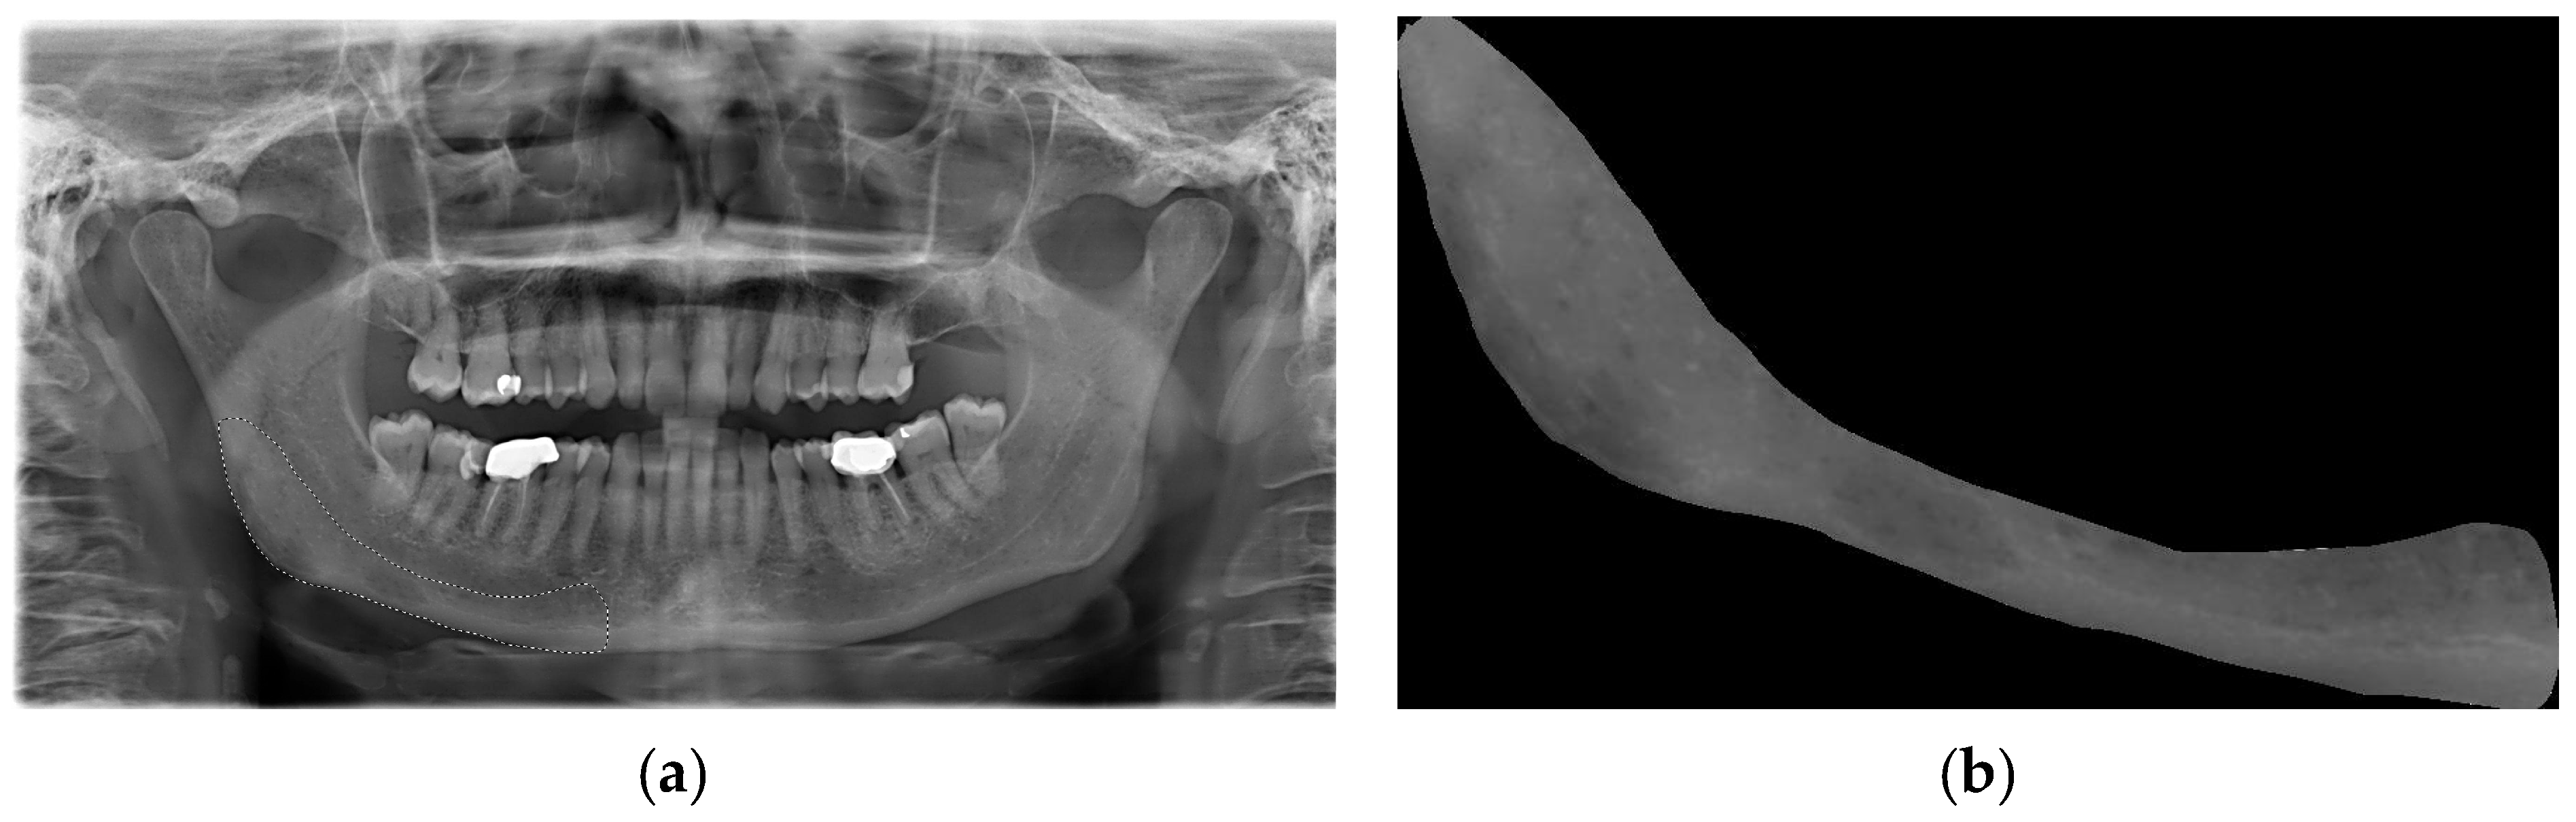

An area that was visible and spread apically to the mandibular canal and distally to the mental foramen, including the angle of the mandible and a portion of the ascending ramus up to the mandibular foramen, was deemed appropriate for inclusion in this study (Figure 1a). This area was subsequently designated as the region of interest (ROI) (Figure 1b). All ROIs were manually traced and cropped from the original OPTs using the “lasso selection” command in the Preview application (Apple Inc., Cupertino, CA, USA). The ROIs were first converted to grayscale and then resized to 256 × 256 pixels to balance image quality and computational efficiency. Histogram equalization was performed on the ROIs to equally distribute the levels of gray intensity with the aim of reducing contrast variations due to possible differences in acquisition protocols. To ensure robust model evaluation and minimize data leakage, the dataset was randomly split at the patient level into training (80%), validation (10%), and test (10%) sets using a reproducible random seed. External validation was conducted on an independent cohort of 56 OPTs from the Parma clinical center. Images with significant artifacts or poor diagnostic quality (motion blur, improper patient positioning) were excluded following a preliminary image quality assessment.

Figure 1. (a) OPT used for region-of-interest (ROI) drawing on the right site of the mandible. (b) Region of interest cropped from the original OPT and used for subsequent analysis.